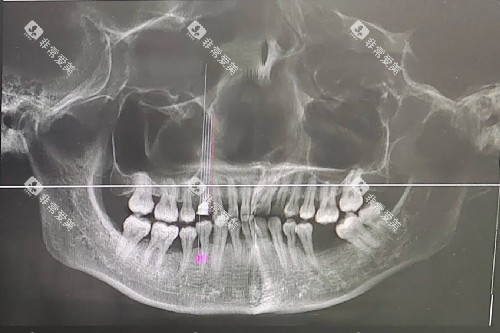

牙槽骨萎缩的诊断需要可靠口腔检查。医生会通过临床检查评估剩余牙齿情况、牙槽骨高度、宽度和密度,以及口腔黏膜健康状况。影像学检查,如口腔CT扫描,可以更好显示牙槽骨的三维结构,评估骨缺失程度和剩余牙槽骨质量,为后续修复方案提供关键依据。